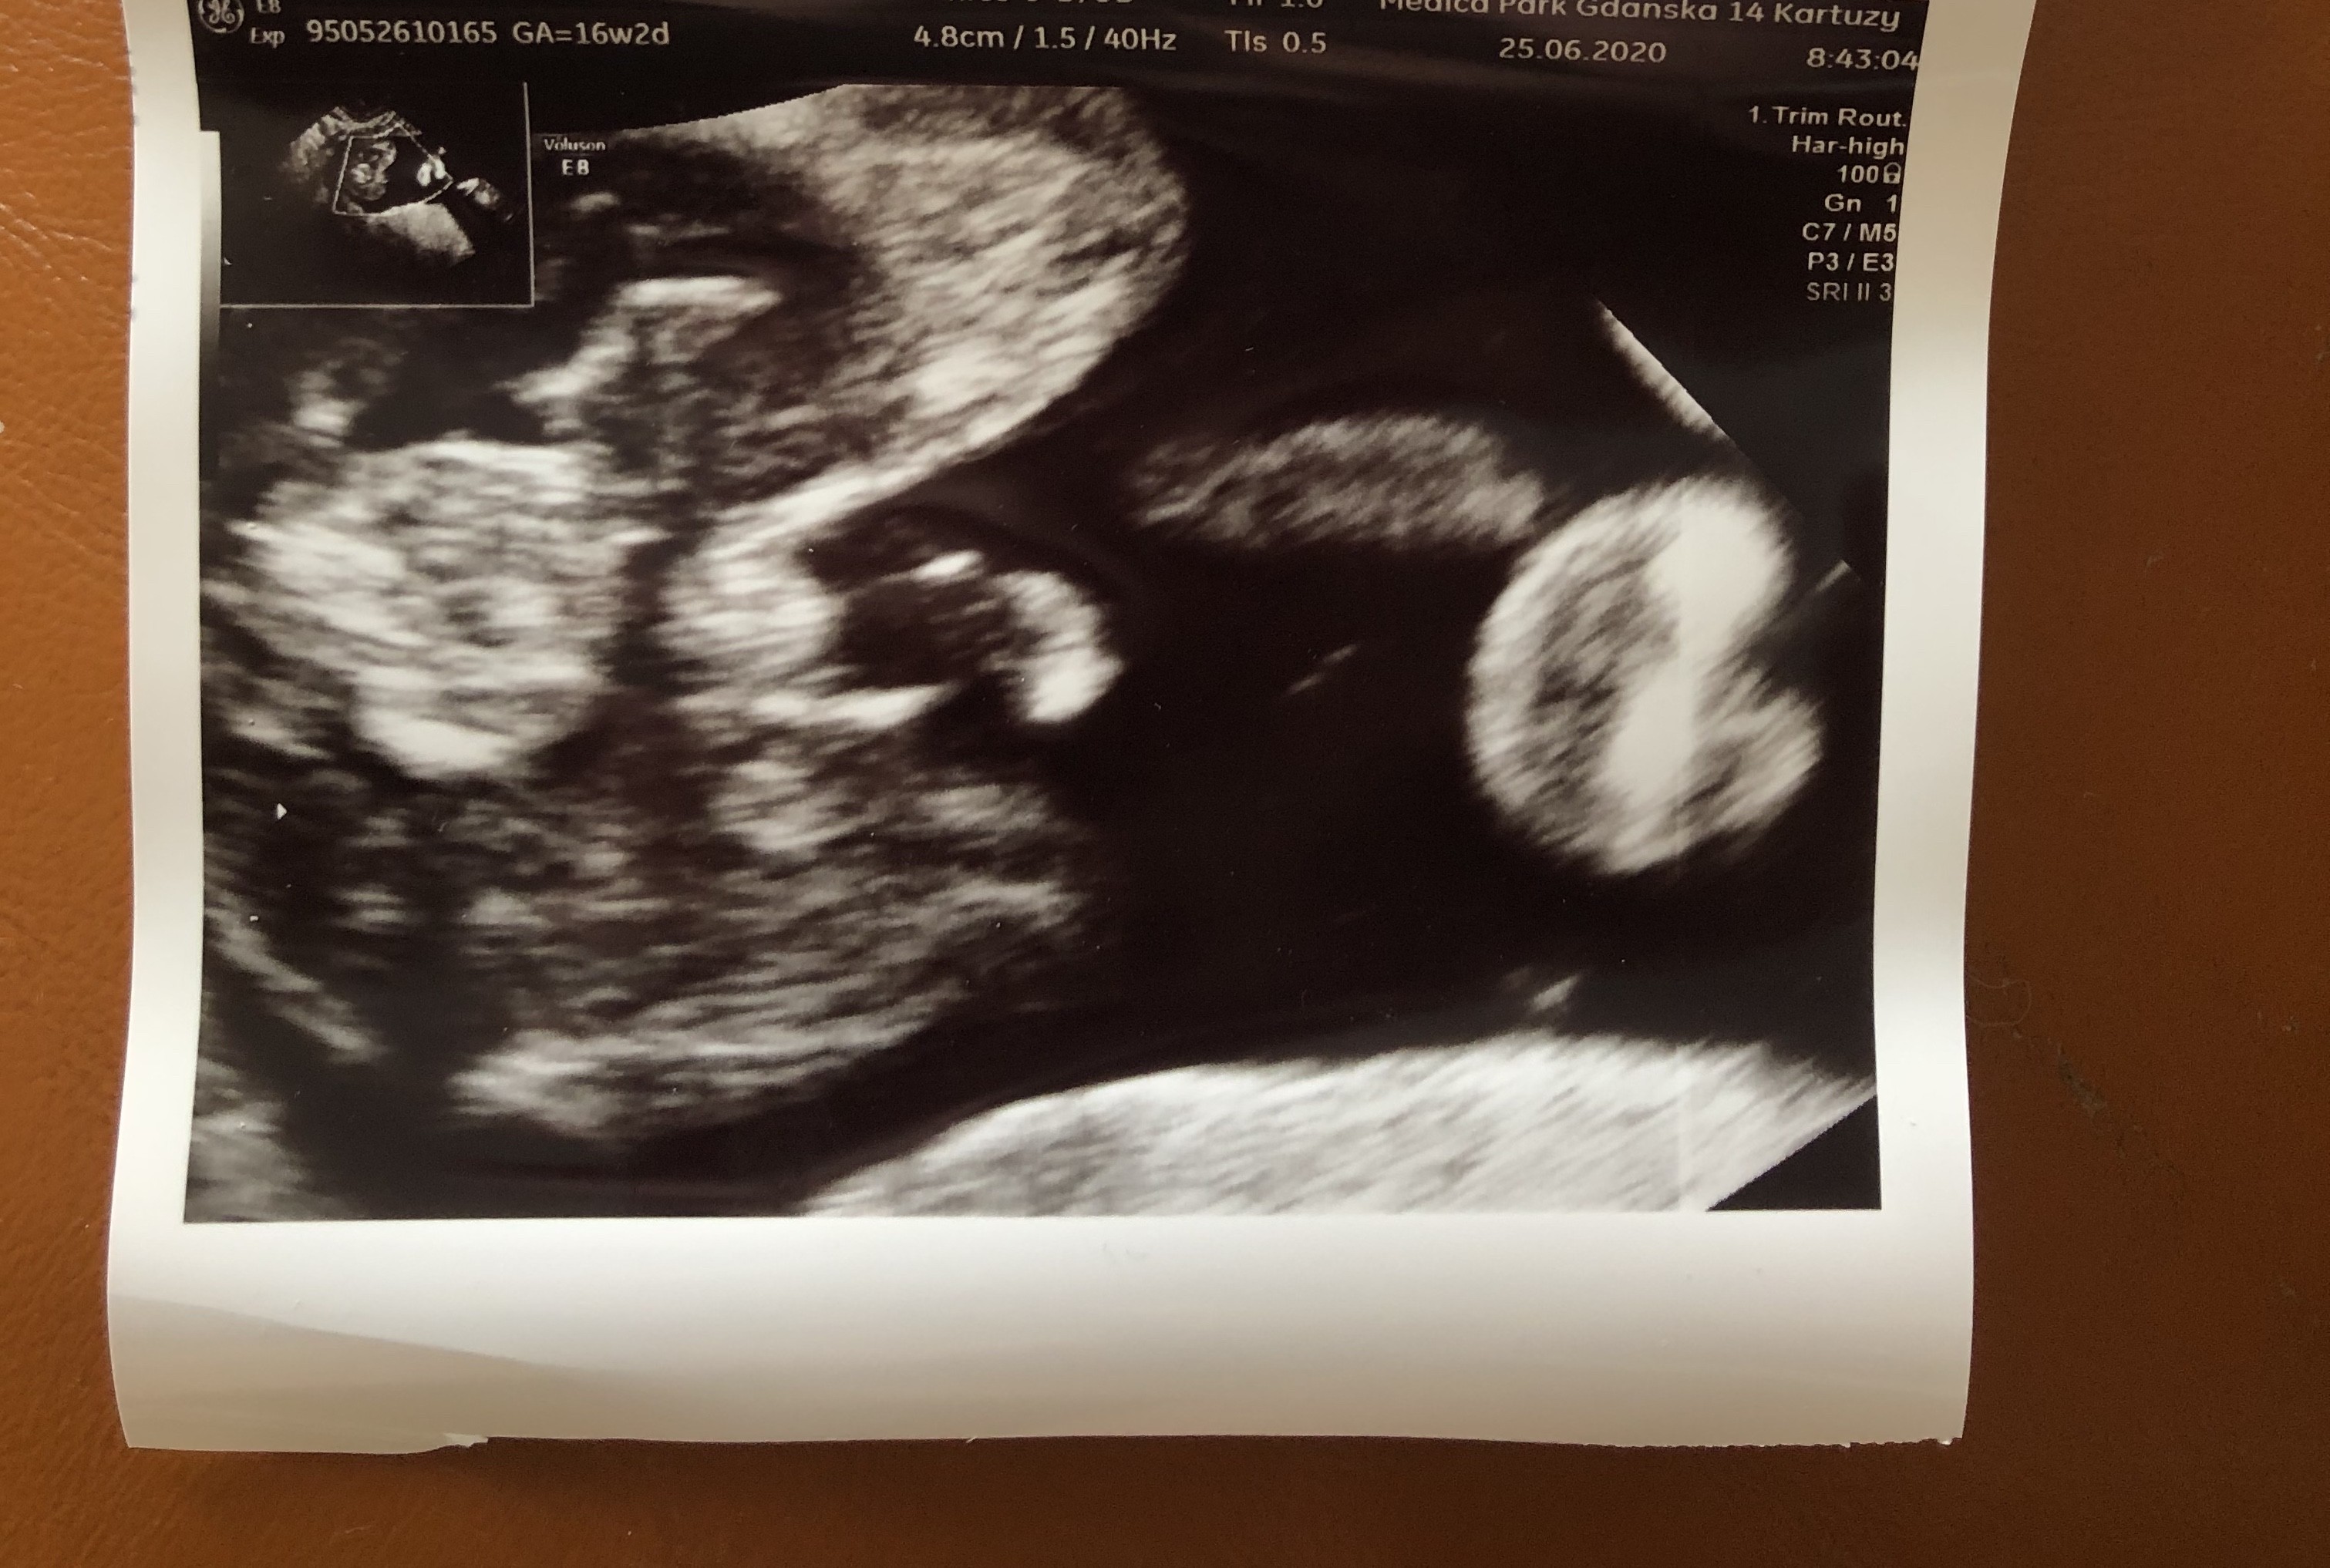

Witam,

a co myślicieo o tym zdjęciu? Lekarz nic nie powiedział. Zdjęcia z 13w4d. Z góry dziękuje :).

Załączniki

• 6FFE9668-C12F-4119-9206-1814B96E9809.jpeg

6FFE9668-C12F-4119-9206-1814B96E9809.jpeg

45,4 KB · Wyświetleń: 186

• E7A2884E-F25F-4DE7-9A46-8818298F3386.jpeg

E7A2884E-F25F-4DE7-9A46-8818298F3386.jpeg

43 KB · Wyświetleń: 201